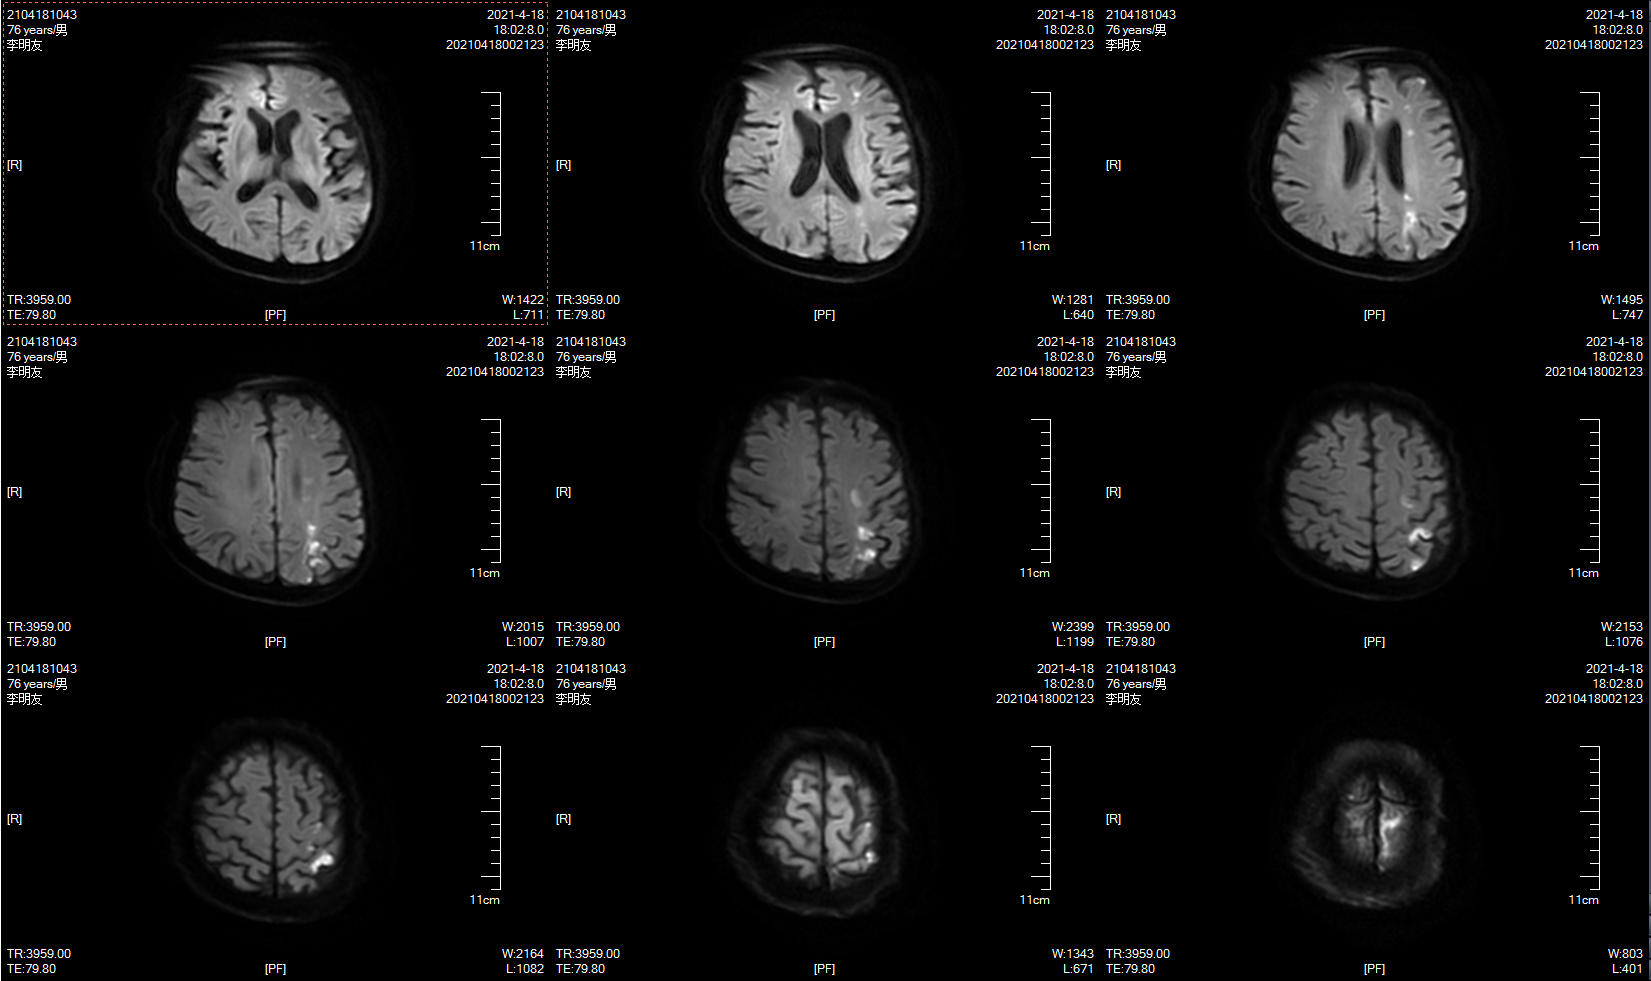

本次MRI示左侧分水岭多发梗死